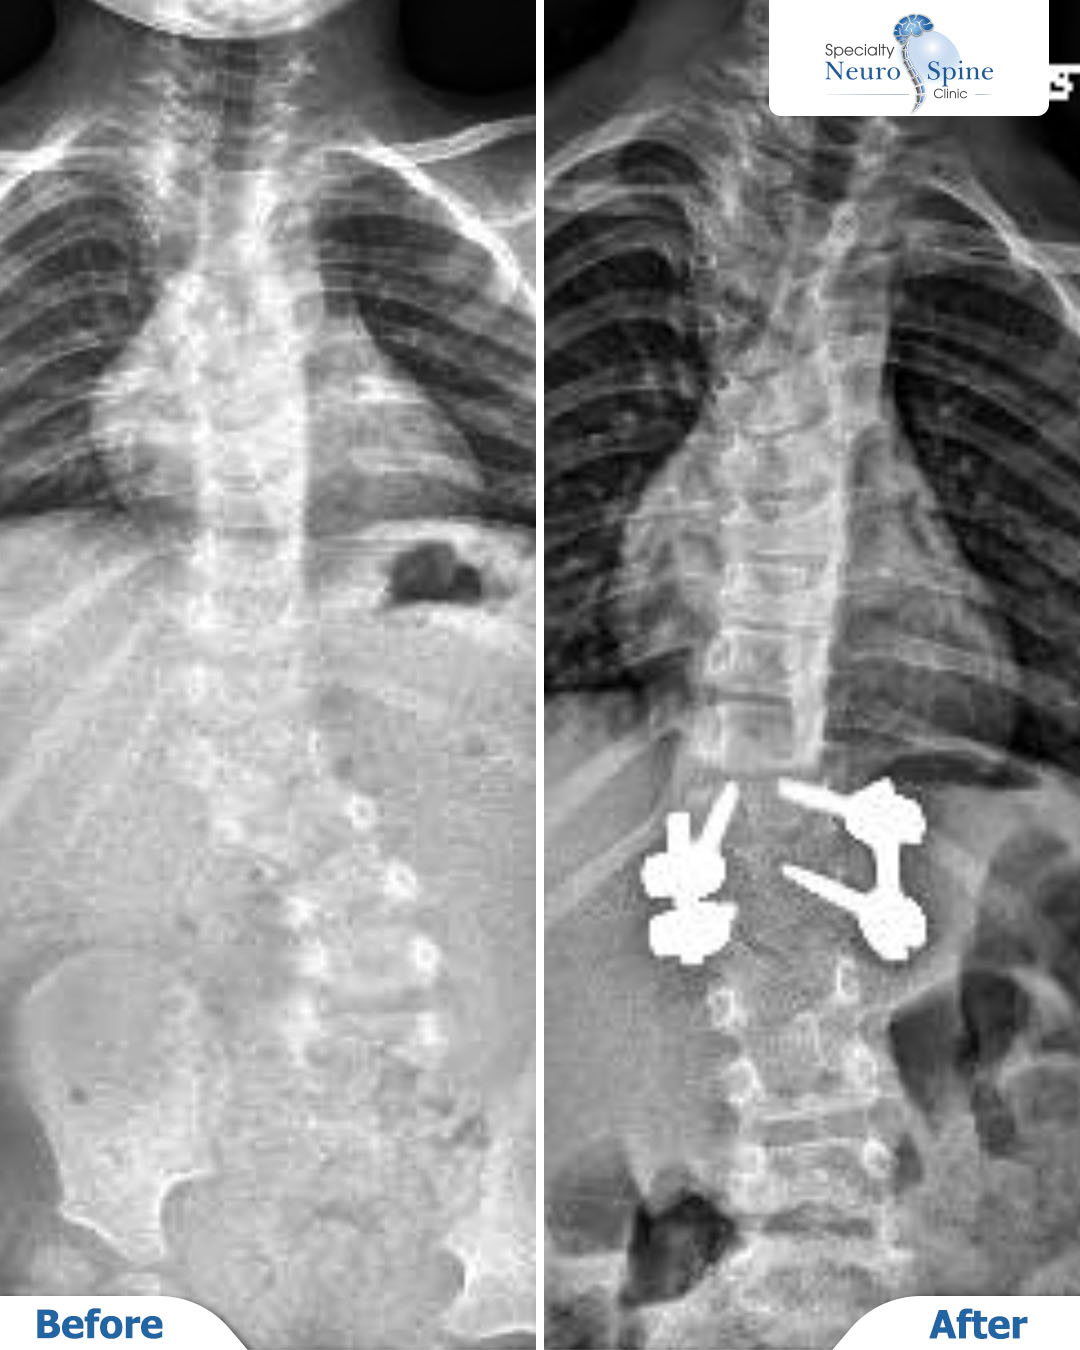

X-ray images showing the condition of our brave patient Sally before and after her spinal deformity correction surgery, which was performed when she was just 3 years old.

The procedure involved correcting the curvature from the twelfth thoracic vertebra (T12) to the first lumbar vertebra (L1). Two years later, the results confirm the success of the surgery, with excellent vertebral alignment and stability.